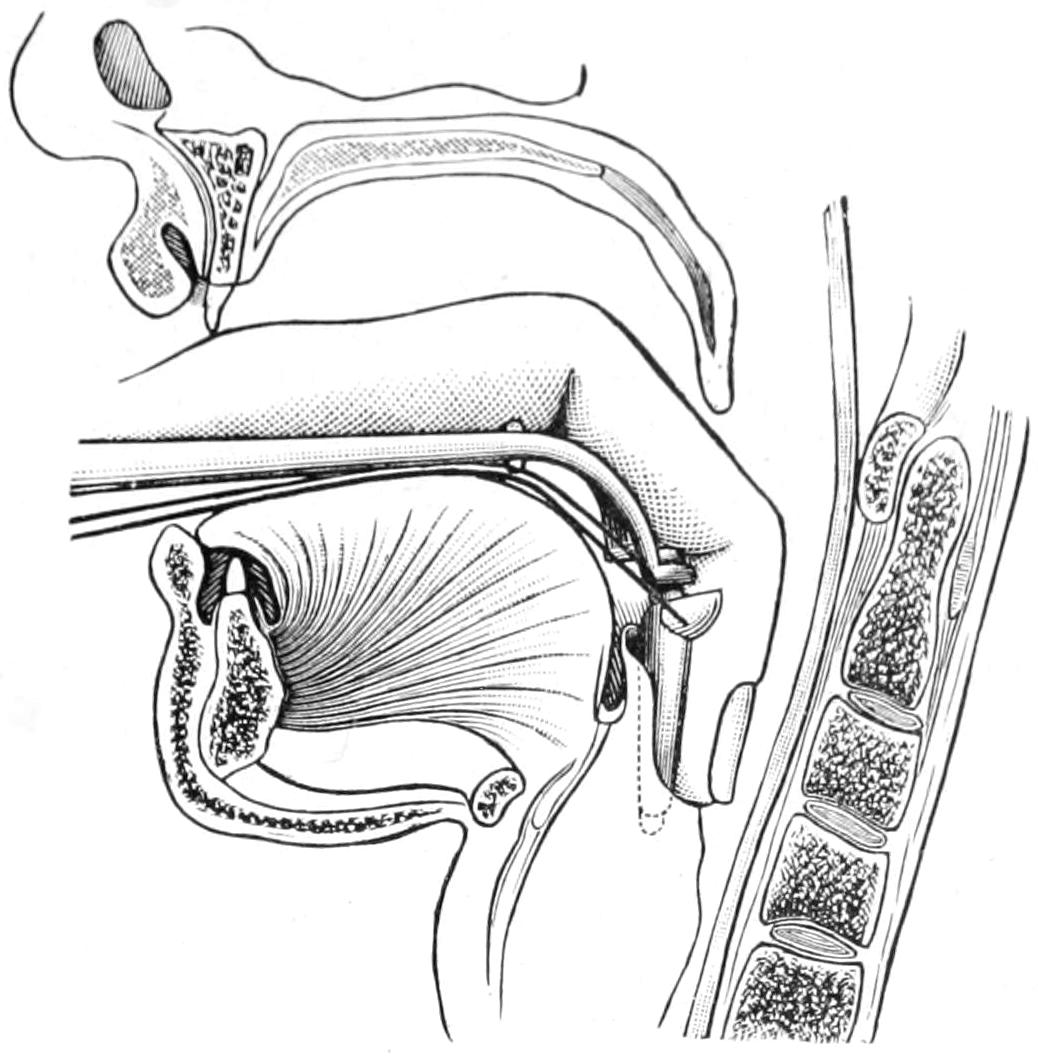

Fig. 1

Congenital hypertrophy: gigantism of both lower extremities. (Case of Dr. Graefe [Sandusky].)